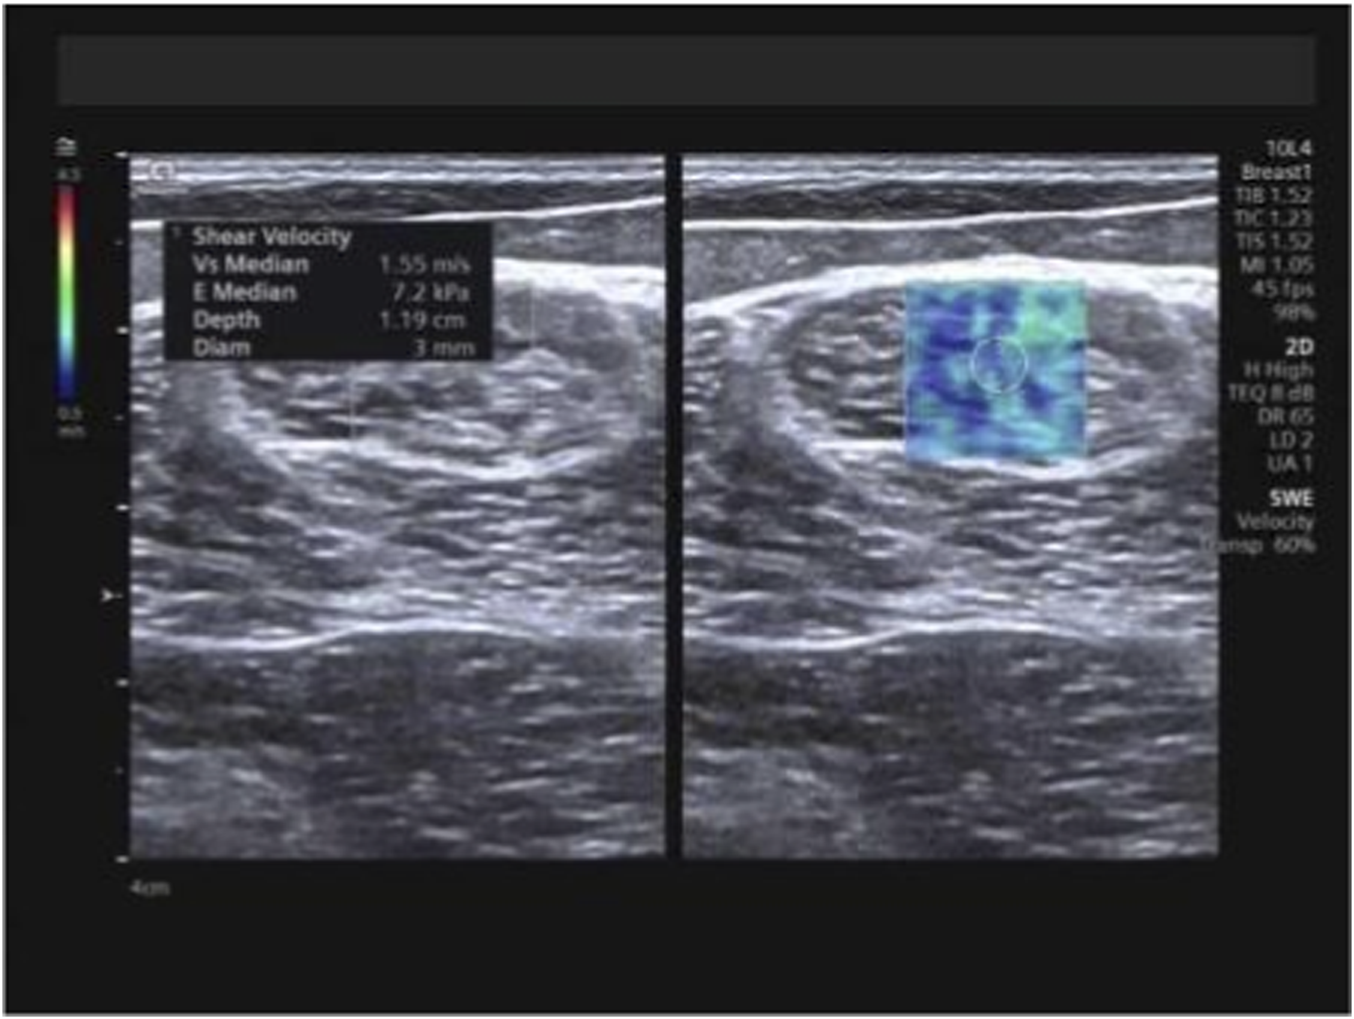

At the identical locations used for muscle thickness measurement, SWE examinations were performed pre-intervention and subsequently after 1 month, 3 months, and 6 months of training, utilizing the aforementioned measurement positions and techniques. Following conventional ultrasound imaging, the system was switched to SWE dual-display mode. The transducer was maintained perpendicular to the skin surface and carefully aligned parallel to the tendon/muscle fibers. The sample box was adjusted, and the image was frozen once stabilized. Using the system’s integrated measurement tools, Emean and SWVmean were measured, with the mean value derived from three consecutive measurements for each parameter (Figures 4–6).

FIGURE 4

Measurement of Emean and SWVmean values for the trapezius. Note: Emean denotes mean Young’s modulus; SWVmean denotes mean shear wave velocity.

FIGURE 6

Measurement of Emean and SWVmean values for the semitendinosus. Note: Emean denotes mean Young’s modulus; SWVmean denotes mean shear wave velocity.